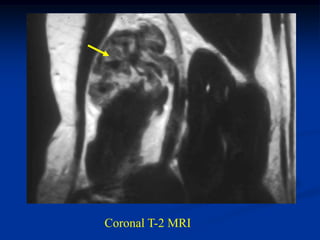

CLASSIC    Case #266   Axial T-2 MRI

41 year male

fibrosarcoma

forearm

Coronal T-2 MRI

Axial T-2 MRI